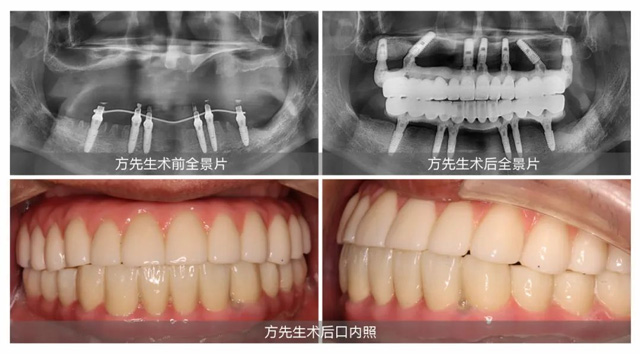

經檢查,方先生因為長期缺牙,牙槽骨萎縮較為嚴重,確實需要植骨治療來增加牙槽骨的穩定性和支撐性,為種植牙“扎根”提供條件。但王鋒醫生表示:“從手術操作的角度來看,植骨和種植體植入可同步進行。這樣可以避免顧客重復手術和麻醉的痛苦,有效節省時間和費用。”王醫生的話,對方先生來說猶如天籟:“看過那么多醫生,只有王鋒醫生非常肯定地告訴我可以當天植骨,當天種牙。”說這話時的方先生仿佛還沉浸在當初的喜悅中。

定下方案第三天,方先生在新橋口腔接受了上半口即刻種植。王鋒醫生在方先生上頜同時完成骨粉和7顆種植體植入,當天為他戴上臨時牙冠,成功解決了困擾方先生許久的缺牙問題。成功圓夢的方先生稱贊道:“只有即刻植骨即刻種植,才是真正的好。”